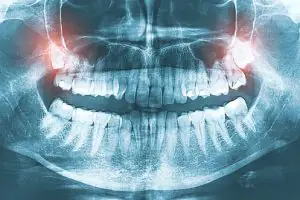

Described wisdom tooth is the tooth that gradually becomes redundant in the process of human evolution; Because the pouch is contused by chewing, the embedding